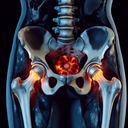

МРТ кульшових суглобів

Магнітно-резонансна томографія (МРТ) кульшових суглобів — це неінвазивний метод діагностики, який використовує магнітні поля та радіохвилі для отримання детальних зображень суглобів і навколишніх м’яких тканин. ### Переваги МРТ кульшових суглобів: 1. **Без радіації**: МРТ не використовує іонізуюче випромінювання, що робить його безпечним для пацієнта...